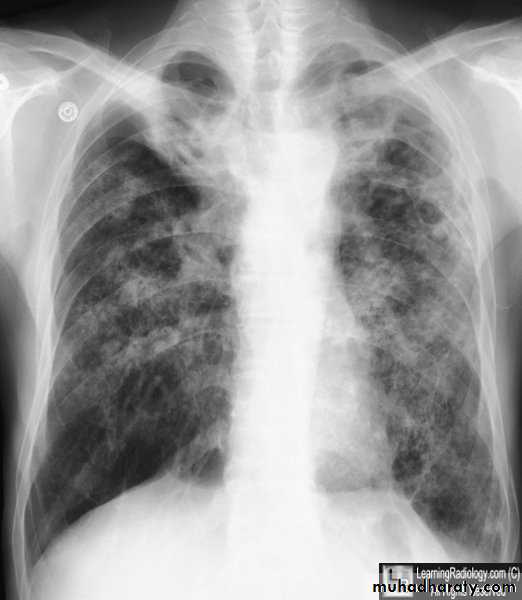

Secondary metastasis

DDX of coin shadow

????????Answer

74. secondary metastasis to the lung ( canon ball appearance )

75. DDX of coin shadow

76. Coin lesion .